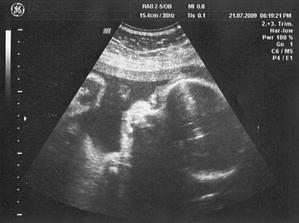

21/7 09 PORADNA 31 + 2 tt - Mája překvapila, místo obvyklé aktivity jen zívala a třela si očička, asi se ukládala ke spánku, takže důkaz že taky někdy spí, doteď sem o tom zatím pochybovala 🙂) ... placenta je opět ok /musím zaklepat/ a máme další fotky do sbírky